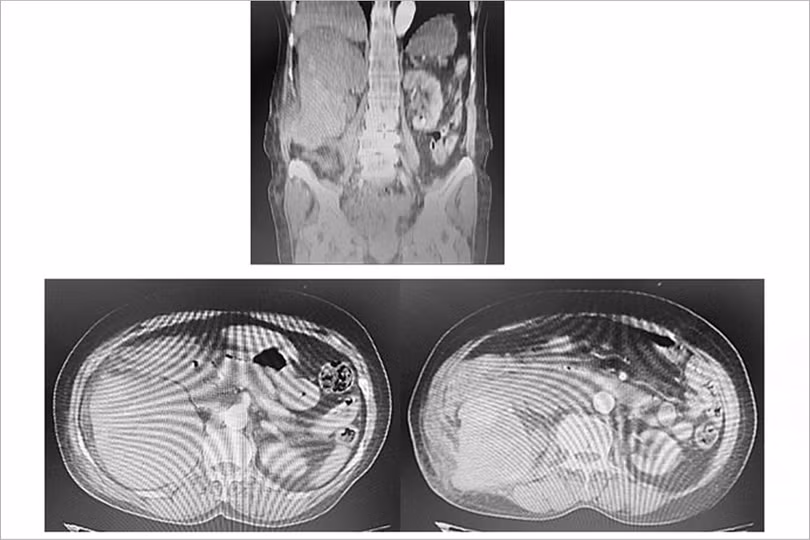

Khi nhập viện, bệnh nhân thấy mệt mỏi nhiều, kèm hoa mắt, chóng mặt. Sau khi thăm khám, bệnh nhân được chẩn đoán sốc mất máu mức độ nặng do vỡ khối u thận phải, sỏi niệu quản phải 1/3 dưới.

Hình ảnh chụp cắt lớp vi tính ổ bụng cấp cứu của bệnh nhân (ảnh BVCC).